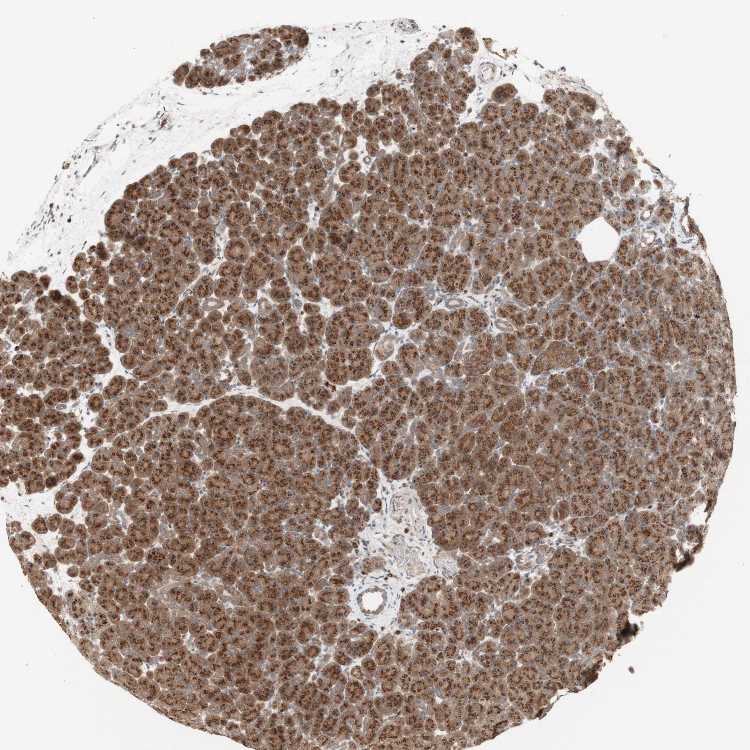

PANCREAS - Antibody stainingi

Antibody staining in the annotated cell types in the current human tissue is reported as not detected, low, medium, or high, based on conventional immunohistochemistry profiling in selected tissues. This score is based on the combination of the staining intensity and fraction of stained cells.

Each image is clickable and will lead to virtual microscopy that enables deeper exploration of all samples and also displays staining intensity scores, fraction scores and subcellular localization as well as patient and tissue information for each sample.

Antibody HPA077163Antibody CAB011713

Exocrine glandular cells HighMedium

Pancreatic endocrine cells LowMedium